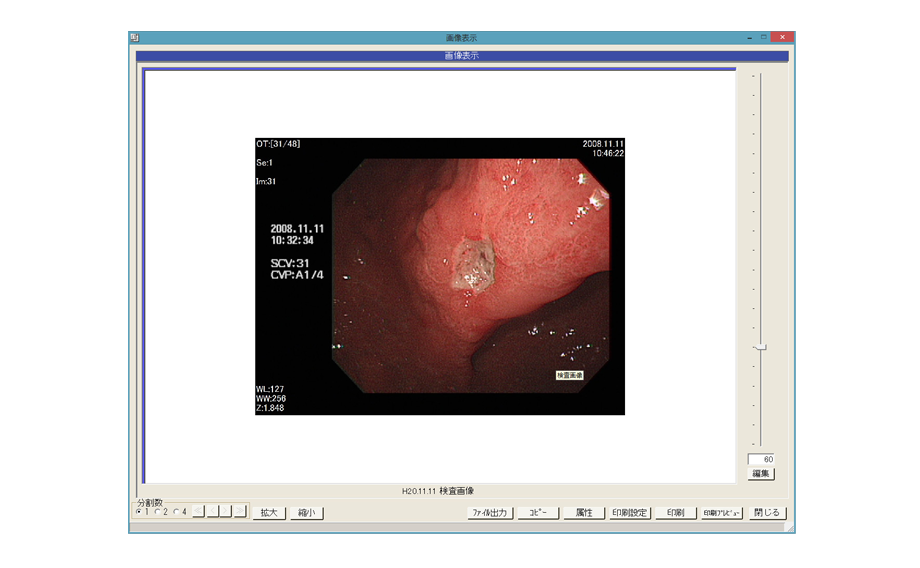

多彩な機能が記録を残す・患者さんに説明するシーンをスマートにサポートします。

※「参照画像表示」・「検査結果表示」・「グラフ表示」・「時系列表示」の機能については、カルテ記録や患者説明の用途でご使用ください。